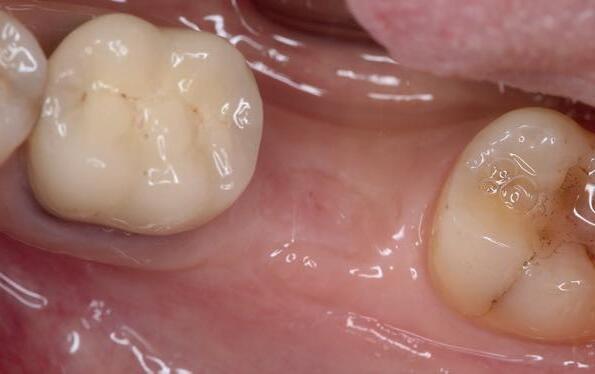

Zes maanden na extractie wordt het implantaat 37 geplaatst. Er is sprake van een goede genezing en de processushoogte en -breedte zijn behouden en opgebouwd. Ook is er zichtbaar gekeratiniseerd weefsel

1 2 Ridge preservation met d-PTFE membranen 35

gewonnen. De wond kan na het plaatsen van een healing abutment primair gesloten worden (Afbeelding 3a-3d).

In afbeeldingen 4a-c is het resultaat drie maanden na het plaatsen van het implantaat te zien. De genezing is volledig en de verwijzer kan de suprastructuur vervaardigen (afbeelding 4a-4c).

In afbeeldingen 5a-d is de implantaatkroon 37 te zien, twee jaar na plaatsing. Op de röntgenfoto is herstel van zowel corticaal als spongieus bot te zien. (De CB-CT was vervaardigd in verband met implantologische indicatie in het naastliggende gebied).

Deze casus illustreert dat er op een voorspelbare manier een ridge preservation procedure uitgevoerd kan worden met een d-PTFE membraan en er daarna voorspelbaar geïmplanteerd kan worden.